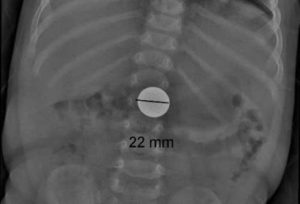

Если ребенок проглотил монету, то в зависимости от ее номинала возможны следующие потенциальные проблемы:

- Монеты номиналом 2 и 10 рублей. Имеют диаметры 23 и 22 миллиметра соответственно. Скорее всего, не попадут в дыхательные пути, однако с большой вероятностью застрянут в горле или пищеводе. При успешном прохождении этих частей покидают тело естественным путем;

- Рентген. Позволяет обнаружить местонахождение монеты;

В отличие от пластмассовых деталей монету легко отследить на рентгене.